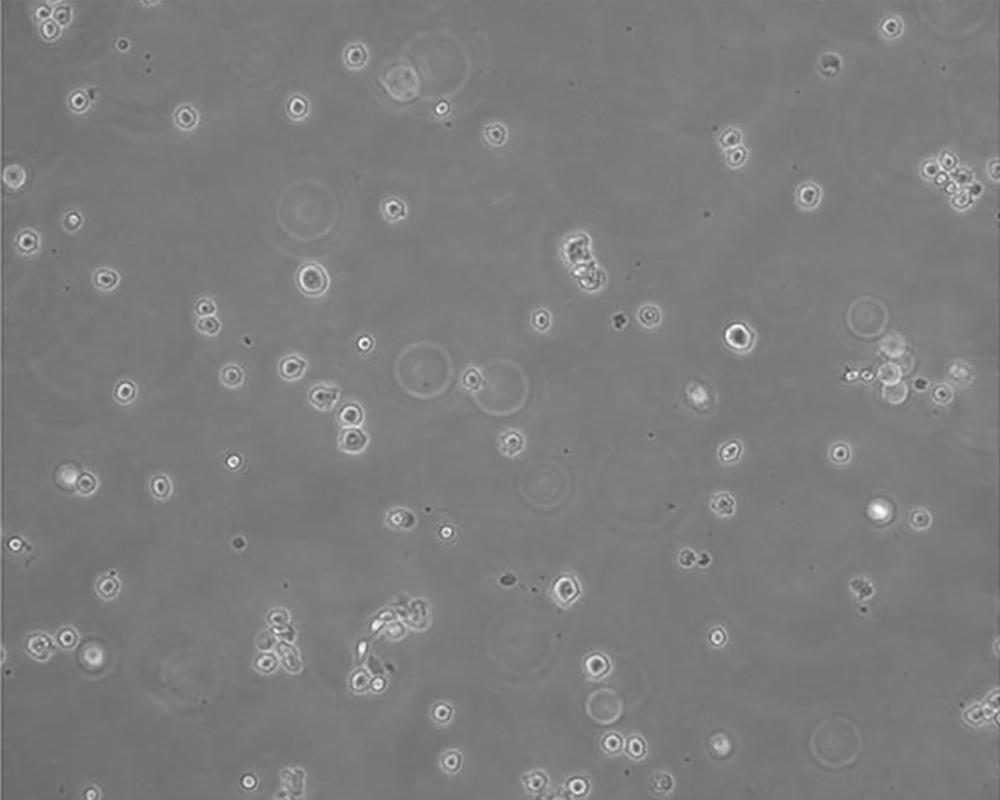

U266 [U266B1]

中文名稱 人多發(fā)性骨髓瘤細胞

生長特性 suspension

形態(tài)特征 lymphoblast

傳代方法 保持細胞密度在1×105~1×106 cells/ml之間,每周換液2~3次

細胞描述 該細胞來源于多發(fā)性骨髓瘤男性患者,表達IgG,分泌IL-6。